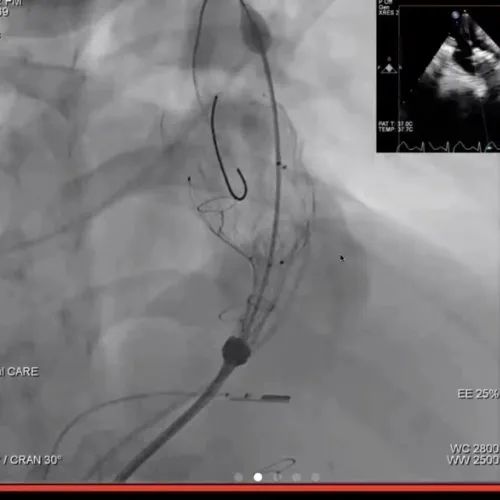

患者是一名21岁青年男性,既往行法洛氏四联症外科跨瓣补片修复术,患有重度肺动脉瓣反流且有显著的右心室、肺动脉扩张及左心室功能障碍。介入手术采用局部麻醉方式,患者清醒状态下穿刺右侧股静脉作为主入路,术中进行了造影及球囊测量,经中美2个团队的再次在线讨论,结合术前CT分析结果,最终精准的选用P34-25(瓣膜腰部直径34mm,长度25mm) VenusP-Valve瓣膜完成植入,即刻造影和超声综合评估显示瓣膜植入位置完美,无反流及残余压差,左右肺动脉分支血流未受影响。术后Scott Lim教授与冯沅教授就手术过程再次进行了讨论,并分享了植入体会。次日好消息传来,超声检查示右室明显变小,无任何肺动脉瓣反流,左室功能恢复正常。术后患者恢复迅速,无并发症发生,患者于术后24小时内,当地时间6月18日出院。

冯沅教授术中指导Scott Lim教授团队进行VenusP-Valve植入

瓣膜植入过程